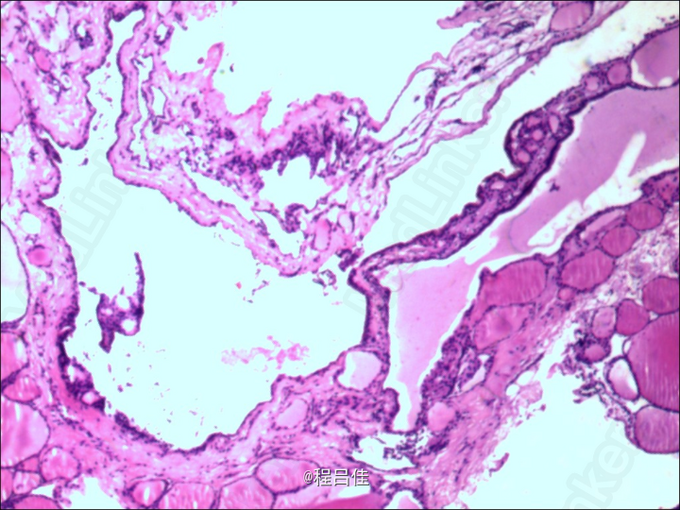

28岁女性患者,因“发现甲状腺肿物2月”入院,不伴局部红肿热痛、吞咽呼吸困难、声嘶、饮水呛咳,也无手抖、多汗、多食、体重下降、心悸等症状。当地医院查甲状腺彩超提示恶性病变,遂至我校附属肿瘤医院行穿刺活检,病理提示纤维及横纹肌组织中见上皮样细胞呈腺样或滤泡状排列,部分滤泡内可见胶质,细胞体积稍增大 ,未见明确神经及血管侵犯,未能除外甲状腺滤泡性癌可能。进一步行甲状腺、胸部CT检查示:甲状腺右叶及峡部病变,侵犯右颈内静脉、右无名静脉、上腔静脉,考虑恶性病变。现为手术治疗而收入我科。既往史无特殊。

术后患者恢复可,定期随访至今。滤泡状腺癌约占甲癌的1/5,中度恶性,病灶多为单发,虽有包膜,但多不完整,常有癌cell浸润。易发血行转移,但侵犯淋巴结则较少,其中特殊类型的Hurthle细胞癌,不吸收放射性碘,预后较差。